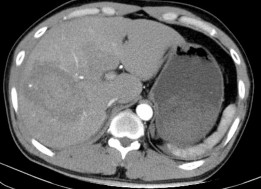

Hình 4.4a: CTG độ IV. Nhu mô HPT VII, VIII có vùng tổn thương ở giữa có phần tăng tỷ trọng dạng máu tụ 96 x 73 mm. nhu mô HPT IV, VI nằm sát bờ gan có vài ổ thoát thuốc cản quang ra ngoài.

Hình 4.4b: CTG độ IV, thì ĐM

Hình4.4c: Thuốc thoát nhiều hơn ở thì muộn

Nguồn: BN Trần Văn T, 37t HS: 008434845